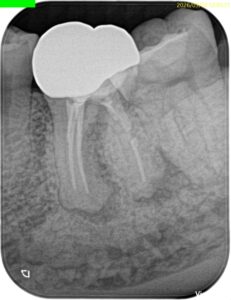

Pre-op Endo test(2026.3.2)

頬側遠心のクラウンマージン部付近にアブセスがある。

2枚のPAでは何もわからない。

診断はついたが、

あなたはこの一連の“絵”に気づいただろうか?

この歯は歯頸部に外部吸収を抱えていたのである。

この2枚のPAでそれがわかるだろうか?

私にはわからない。

穿孔しているのだろうか?とまず思ったが、CBCTをみてそれは穿孔でなく外部吸収の可能性が高いと判断できた。